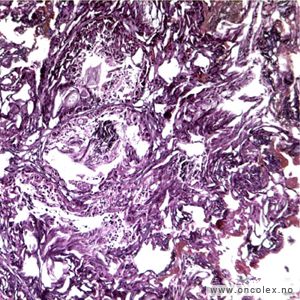

Bildeeksempler av vevsprøver

Gleasongraderinger

Ved prostatakreft anvendes et særskilt graderingssystem som ble beskrevet av patologen Donald Gleason i 1966. Dette samsvarer sterkt til prognosen. I motsetning til WHO baserer Gleasongradering/Gleason score (GS) seg kun på kjertlenes arkitektur og cellenes sammensetning, ikke cellenes atypi. De senere årene har ISUP gradering kommet i bruk, det er forsåvidt en forenkling av GS med et tall fra 1-5 hvor ISUP 1 = GS6, ISUP 2 = GS 7a, ISUP 3 = GS7b, ISUP 4 = GS8 og ISUP 5 = GS 9 og 10.

De mest aggressive svulstene har Gleasongrad 5, score 9–10 = ISUP 5. Gleason score (GS) angis for hver nålebiopsi som summen av den dominerende og sekundære grad. Den sekundære grad oppgis bare dersom den utgjør mer enn 5%.

Tertiær Gleasongrad 4 eller 5 rapporteres selv om de utgjør < 5%. Ved Gleasonscore 7b (4+3) er den dominerende Gleasongrad 4. Disse har dårligere prognose enn Gleasonscore 7a. Svulster med Gleasonscore 6 er lavgradig, Gleasonscore 7 er intermediære, mens Gleasonscore 8–10 er høygradige.